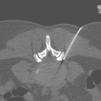

La energía láser se emitió a una potencia de 15W en pulsos de 0,5-1 segundo seguidos por una pausa de 4-5 segundos para permitir la disipación del calor y evitar o minimizar el dolor que pudiera causar el calor. Es fundamental una cuidadosa monitorización del dolor del paciente, de modo que la frecuencia de pulso debe incrementarse si el paciente experimenta molestias. La dosis de energía láser osciló entre 1.000 y 2.000 julios, dependiendo del nivel del disco afectado, y también se valoró la formación del gas vaporizado intradiscal (fig. 4). Todos los procedimientos de DPDL fueron realizados por dos radiólogos intervencionistas. Cada paciente fue sometido a una única DPDL.